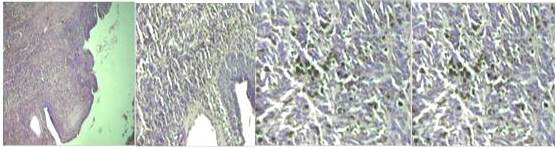

Revisión de láminas D08-539: tumor maligno poco diferenciado, sólido, difuso, de alto grado citológico de patrón arquitectural en áreas sarcomatoso en otras epitelioides, sin evidencias de invasión vascular hemática, ni linfática en la muestra examinada.

Nota: la neoplasia presenta además, pigmento parduzco intracelular y extracelular que impresiona no corresponder a hemosiderina, lo que nos hace sugerir el diagnóstico de melanoma maligno. (Figura 1))